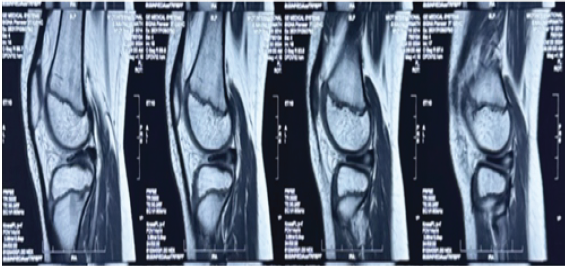

• Preoperative MRI scans were utilized to evaluate the meniscal morphology, tear configuration and associated intra-articular pathology (Fig. 1). Such key procedural steps like the meniscal inside-out repair and the saucerization and anatomical restoration were recorded using the intraoperative arthroscopic images (Fig. 2).

Figure 1: Preoperative MRI of Discoid Meniscus.